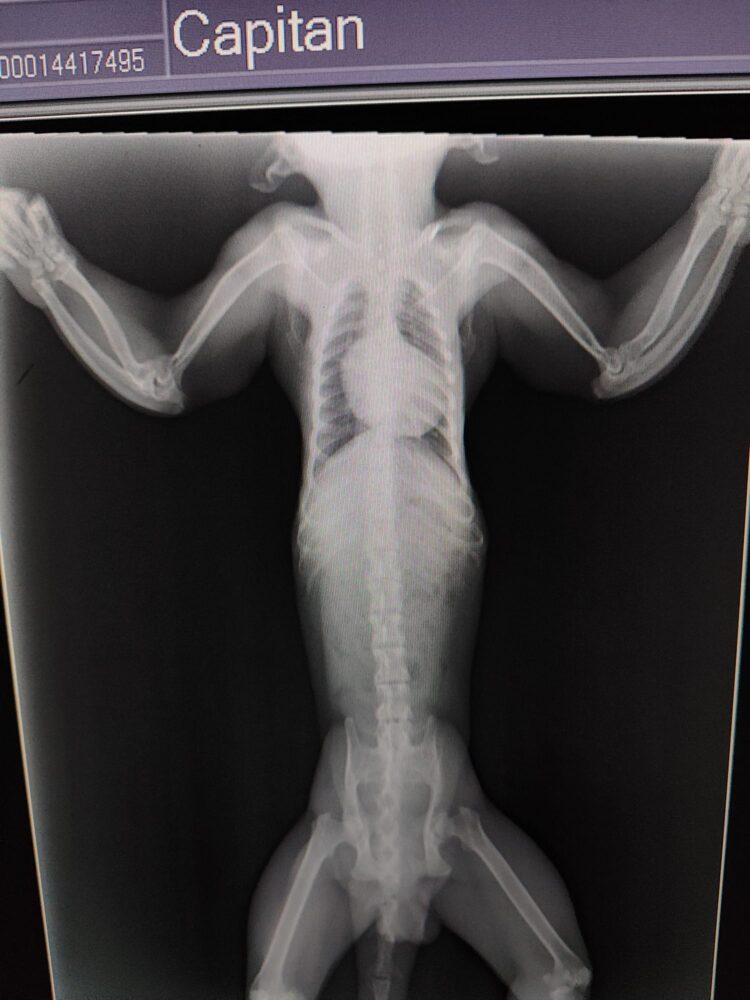

X-rays also showed signs of metabolic bone disease. This condition is caused by poor nutrition and a lack of exposure to sunlight, which is necessary for the production of vitamin D. This vitamin plays an important role in the absorption of calcium and the formation and density of bones.

If bone metabolism is disrupted, bones cannot develop properly. This causes them to become brittle and grow crooked.

Capitán’s ulna and radius (forearm bones) are deformed. He also appears to have an old fracture in his left forearm. Both deformities can be explained by low bone density. The bones in both his upper arms are also poorly developed.

"The consequences of a metabolic bone disease cannot be cured or reversed. They are permanent. Capitán will have to live with thin upper arm bones and deformed forearms for the rest of his life. There is also a risk of fractures and the development of osteoarthritis, not to mention the pain this may cause him."

Sonsoles Hernández, veterinarian at AAP Spain.

Osteoarthritis and deformities in the elbows

X-rays showed that he also has osteoarthritis and deformities in his elbows. This joint wear and partial deformation of the elbow bones may also have been caused by a metabolic bone disease.